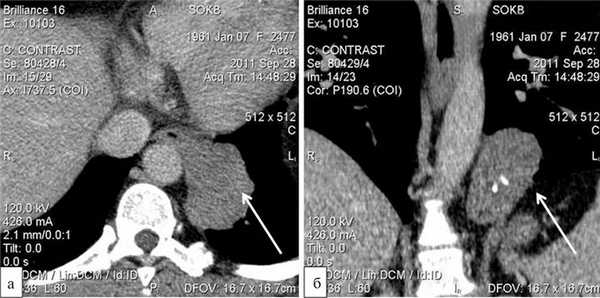

Больная Ш., 50 лет, госпитализирована в отделение торакальной хирургии областной больницы в плановом порядке 27.09.11. Жалоб, характерных для заболеваний пищевода, не предъявляла. Из анамнеза известно, что около 1 мес назад при прохождении ежегодной флюорографии были выявлены изменения в органах грудной клетки, послужившие основанием для дальнейшего обследования. При компьютерной томографии органов грудной клетки определялось опухолевое образование в наддиафрагмальном сегменте пищевода, овоидной формы, размером 12×7 см, исходящее из мышечной стенки органа, с включениями кальцинатов, большей частью располагающееся в левой плевральной полости. Морфоденситометрические характеристики образования наиболее соответствовали гигантской лейомиоме пищевода (рис. 1). Больная консультирована торакальным хирургом и направлена на госпитализацию с целью оперативного лечения.

Рис. 1. Компьютерные томограммы органов грудной клетки в аксиальном (а) и фронтальном (б) срезах. Стрелками указана гигантская лейомиома наддиафрагмального сегмента пищевода.